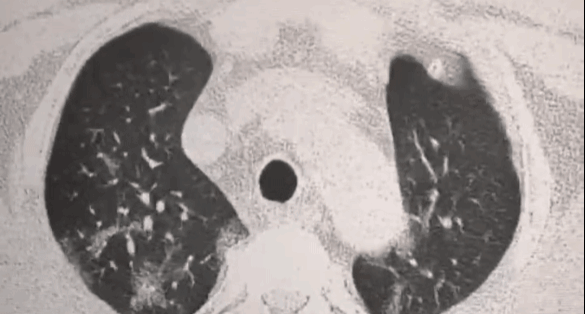

就会发展成肺结节,肺纤维化,甚至肺癌

受损的肺细胞会形成肺结节

进而引发肺部纤维化、甚至肺ai

医学上对肺结节没有特效药

一般只能手术切除

缩小、控制肺结节,预防并改善肺部纤维化

肺部有很多结节

很多人吃完一周后,肺结节真的消失了!

张女士于2021年11月份检查出4.2MM左肺混合磨现璃结节,右肺3.8MM纯磨玻璃结节。

服用4瓶美国康美森槲皮素周期,复查发现结节已经完全消除。无明显异常,不咳嗽了痰也变少了。